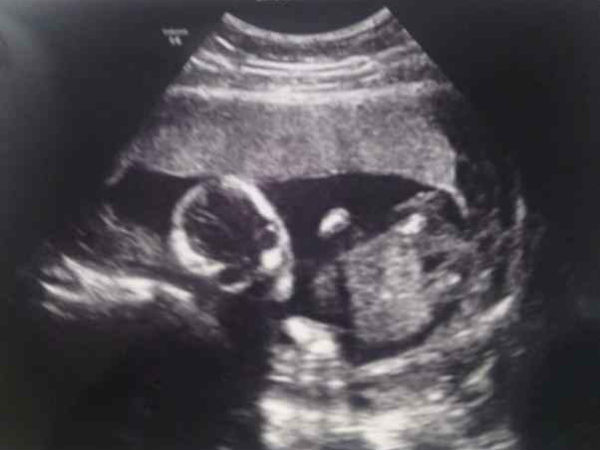

చిత్రం #2 అది ఇక్కడ కనిపిస్తుందా?

పుట్టక ముందే శిశువు భంగిమ కనిపిస్తుందా? సరే, అతను/ఆమె లా ఖచ్చితంగా ఒకరు ఉంటె పిండం భంగిమ ఒక అనుకూలంగా కనిపించవచ్చు! కళ్ళు అటూఇటూ కదిలిస్తూ చాలామంది ఖచ్చితంగా నిద్రపోరు!